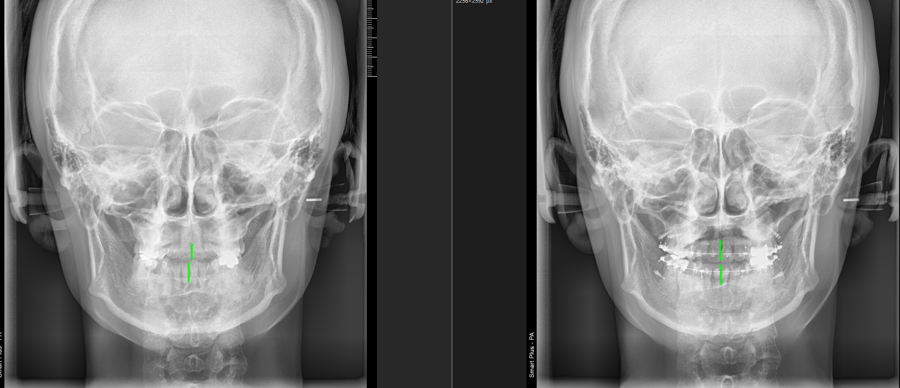

이 경우 오른쪽아래 어금니가 틀어져서

다물때 그부분이 먼저 닿으면서 턱 전체가

Deviation 즉 휘어짐이 나타났기 때문에

치아 배열만 개선해도

비대칭개선과 턱관절문제의 개선이 있을 수 있었습니다

이때 비대칭의 요소가 뼈인지 치아인지 턱관절인지. 어떤우선순위로 나타난 것인지는

치아나 엑스레이 타진 등을 통해 증거를 수집해서 알게 되는 것 같습니다